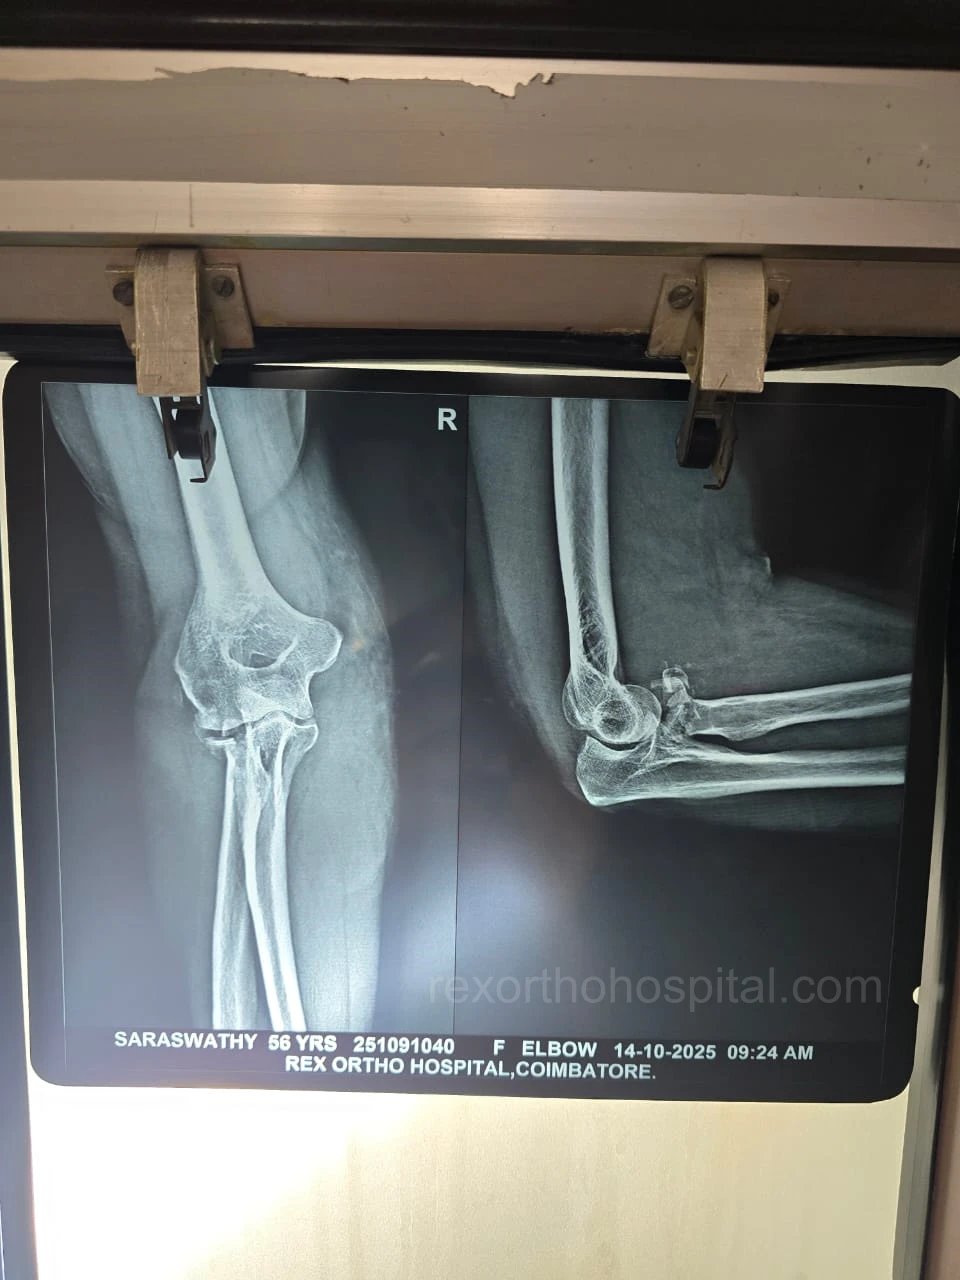

Elbow stiffness treatment aims to restore smooth movement and reduce pain caused by injury, arthritis, or long-term immobility. Our approach improves flexibility and helps regain everyday function.

From diagnosis to surgery and recovery, our team ensures you receive expert treatment and individual attention throughout your treatment journey